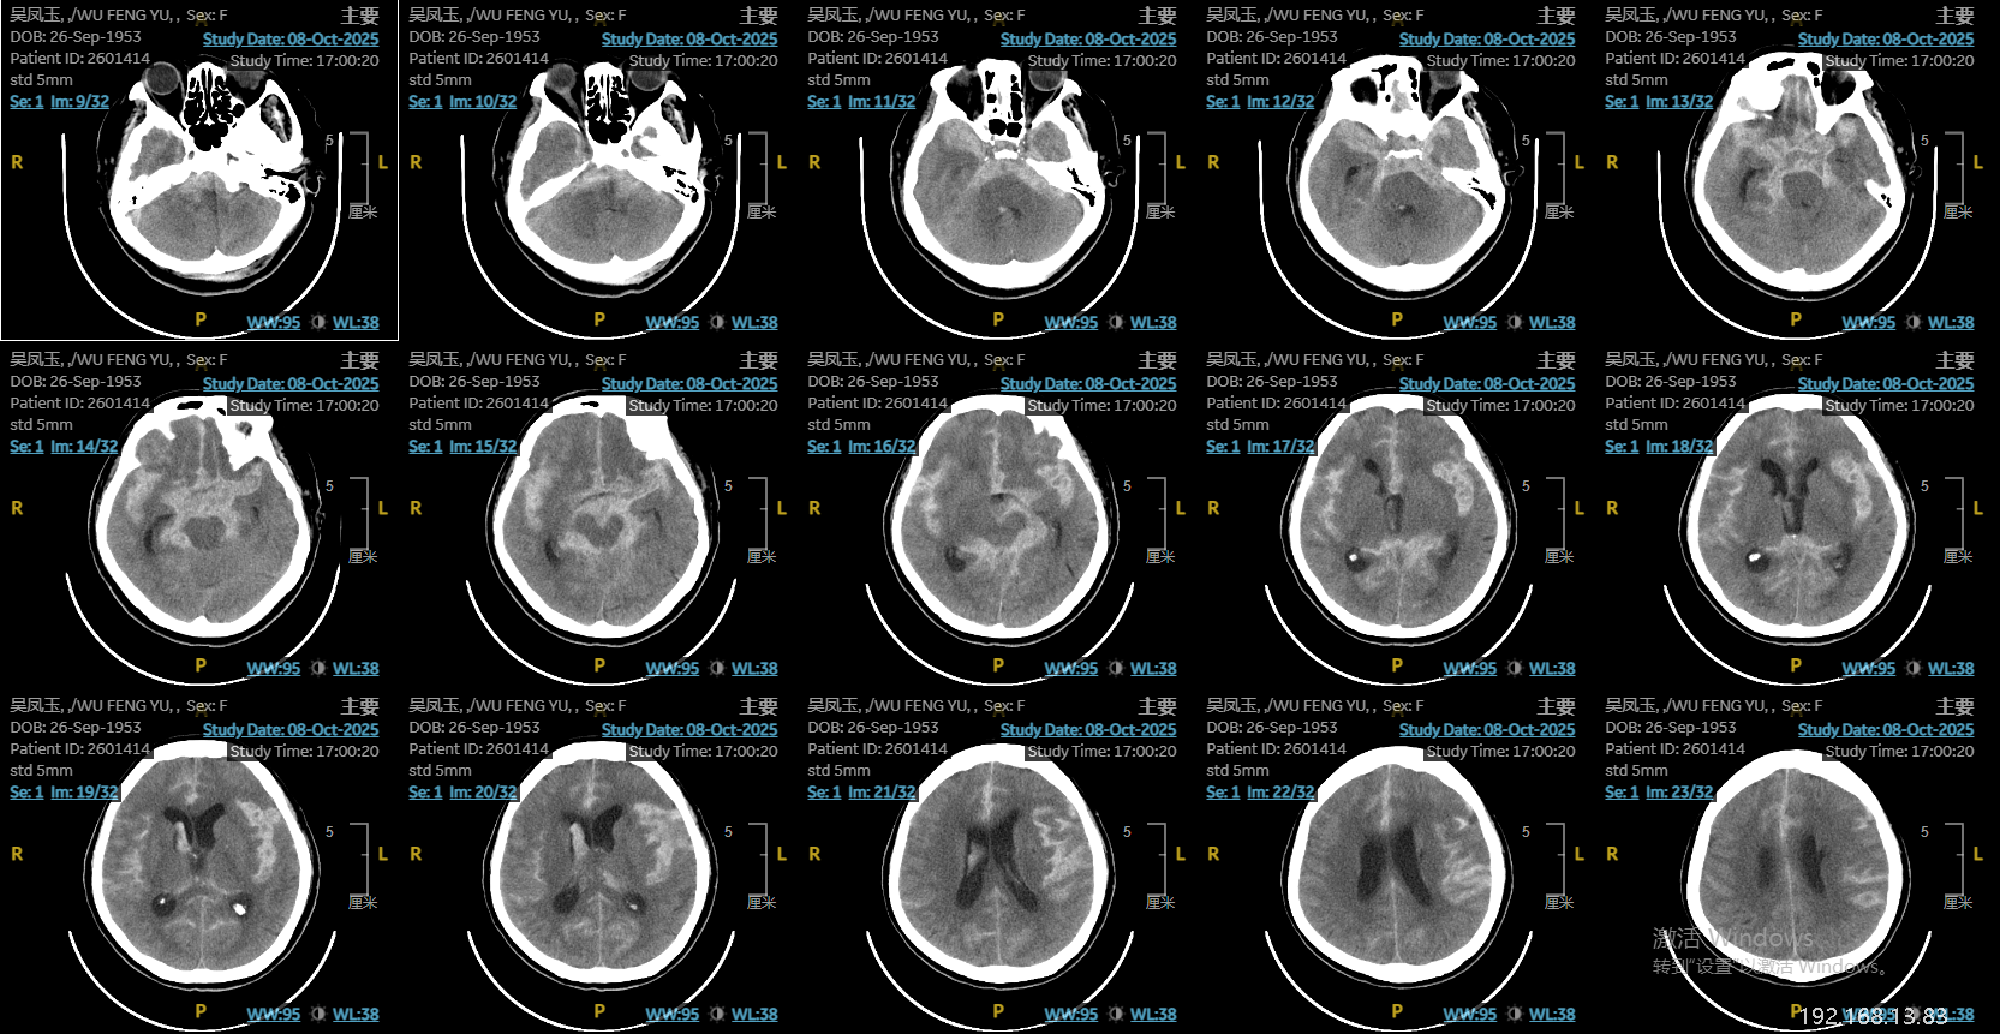

微小动脉瘤1例

患者老年女性,72岁,昏迷入院。